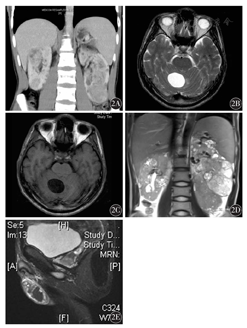

例2,男性,29岁。2007年8月底体检腹部超声示:双肾多发性局灶性多囊性或潜在多囊性病灶;胰腺多发性囊肿;左侧肾上腺区多囊性病灶;双侧附睾头多囊性病灶。因多发囊肿不宜手术处理,密切随访。2012年12月19日复查CT:双肾囊肿,双肾癌变可能,胰腺囊肿(图2A),建议穿刺活组织检查,患者及家属拒绝。2014年12月10日患者头晕伴恶心、呕吐,伴步态不稳,休息后稍缓解;头颅MRI示:小脑囊性占位。2014年12月24日患者再次出现头晕、恶心,喷射状呕吐;急查头颅MRI示:右侧小脑半球囊实性占位,囊壁不强化,上极可见强化结节(图2B、图2C)。入院后予脱水、对症支持治疗后症状缓解,2014年12月31日在全身麻醉下行"经枕后正中入路肿瘤切除术" ,术后病理:小脑血管母细胞瘤(WHOⅠ级)。免疫组织化学:GFAP-,EMA-,Olig-2-,Ki-67+ 2 %,CD34++,Syn-,α-inhibin 1+,D2-40-。2015年6月19日复查CT:双肾多发占位明显增大(图2D、图2E)。患者为小脑血管母细胞瘤、胰腺、肾上腺囊肿及双肾占位(VHL 1型),放弃继续诊治,仍在随访中。

2A:腹部CT,双肾多发占位,左侧肾上腺、双肾多发囊肿;2B:颅脑MRI,小脑半球T2WI以长T2为主的信号区;2C:颅脑MRI,小脑半球T1WI低信号区;2D:腹部MRI,双肾多发占位,较前明显增大,左侧肾上腺、双肾多发囊肿;2E:MRI附睾囊肿